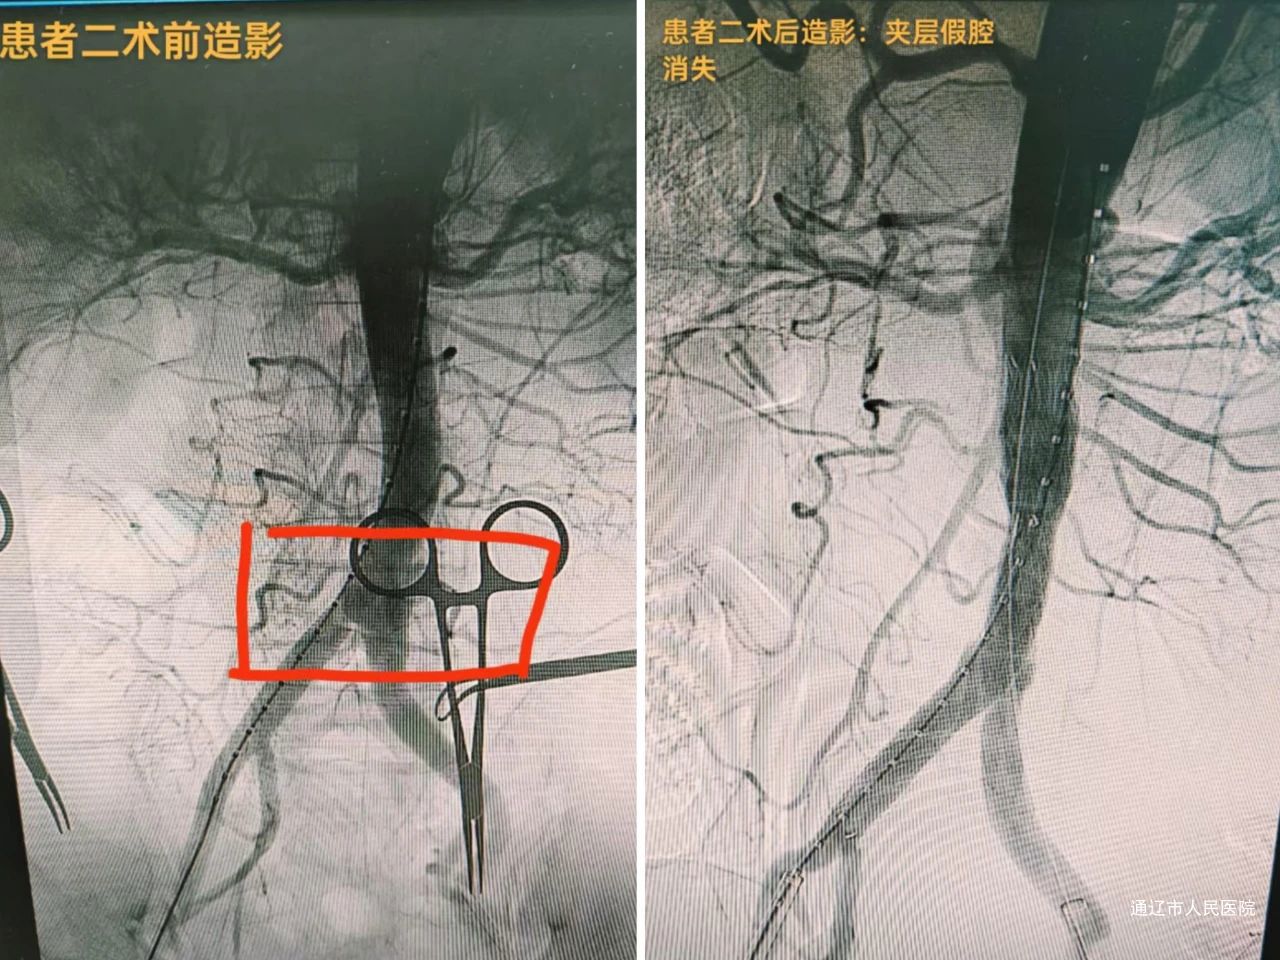

主动脉瘤与主动脉夹层属于致死率极高危重症,传统开放手术创伤大、风险高,尤其对于高龄、基础疾病多、解剖结构复杂的患者,治疗难度极大。血管肿瘤介入科团队依托先进的数字减影血管造影(DSA)设备,结合个体化三维手术规划,通过微创腔内修复术(EVAR/TEVAR),成功为多名高危患者解除生命威胁,展现了介入技术的突破性优势。

复杂胸主动脉瘤患者王某,因肺功能差被多家医院判定为开放手术禁忌症,血管肿瘤介入科团队仅通过双侧股动脉穿刺预制缝合器技术完成“胸主动脉瘤腔内修复术”,术后次日即可下地正常活动;腹主动脉夹层患者李某某发病时出现下肢缺血、尿量减少等器官灌注不足症状,经手术重建主动脉真腔后肢体温暖、尿量恢复。“没想到不用开刀就能治好这么严重的病,是介入技术给了我第二次生命!”两位患者康复出院时,难掩感激之情。